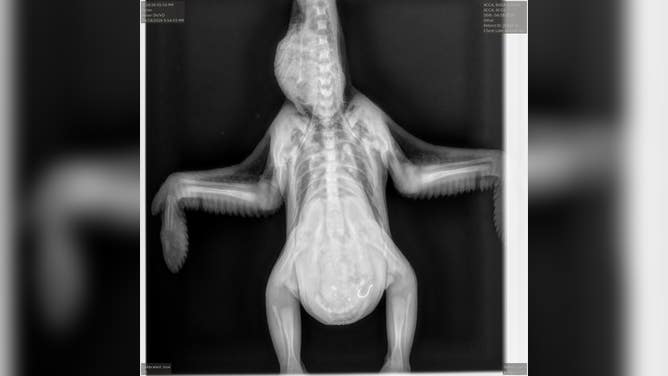

An X-ray of the eaglet, showing the fishhook in its stomach.

(Dr. Jesse Fallon/Avian Conservation Center of Appalachia / FOX Weather)

The eaglet's X-ray, showing the fishhook in its stomach.